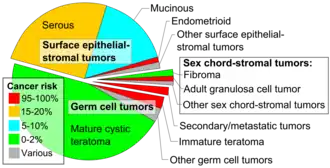

An immature teratoma is a teratoma that contains anaplastic immature elements, and is often synonymous with malignant teratoma.[1] A teratoma is a tumor of germ cell origin, containing tissues from more than one germ cell line,[2][3][4] It can be ovarian or testicular in its origin.[4] and are almost always benign.[5] An immature teratoma is thus a very rare tumor, representing 1% of all teratomas, 1% of all ovarian cancers, and 35.6% of malignant ovarian germ cell tumors.[6] It displays a specific age of incidence, occurring most frequently in the first two decades of life and almost never after menopause.[4] Unlike a mature cystic teratoma, an immature teratoma contains immature or embryonic structures. It can coexist with mature cystic teratomas and can constitute of a combination of both adult and embryonic tissue.[7][8] The most common symptoms noted are abdominal distension and masses.[9] Prognosis and treatment options vary and largely depend on grade, stage and karyotype of the tumor itself.